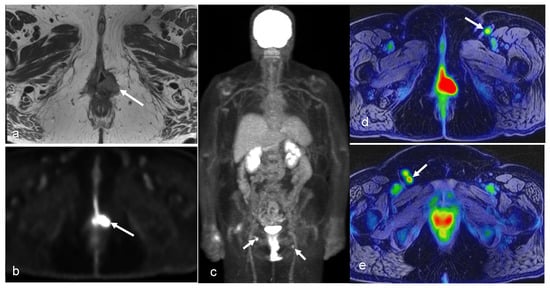

3.4. Vaginal and Vulvar Cancers

- Chow, L.; Tsui, B.Q.; Bahrami, S.; Masamed, R.; Memarzadeh, S.; Raman, S.S.; Patel, M.K. Gynecologic tumor board: A radiologist’s guide to vulvar and vaginal malignancies. Abdom. Radiol. 2021, 46, 5669–5686. [Google Scholar] [CrossRef] [PubMed]

- Cohn, D.E.; Dehdashti, F.; Gibb, R.K.; Mutch, D.G.; Rader, J.S.; Siegel, B.A.; Herzog, T.J. Prospective evaluation of positron emission tomography for the detection of groin node metastases from vulvar cancer. Gynecol. Oncol. 2002, 85, 179–184. [Google Scholar] [CrossRef]

- Rufini, V.; Garganese, G.; Ieria, F.P.; Pasciuto, T.; Fragomeni, S.M.; Gui, B.; Florit, A.; Inzani, F.; Zannoni, G.F.; Scambia, G.; et al. Diagnostic performance of preoperative [18F]FDG-PET/CT for lymph node staging in vulvar cancer: A large single-centre study. Eur. J. Nucl. Med. Mol. Imaging 2021, 48, 3303–3314. [Google Scholar] [CrossRef] [PubMed]